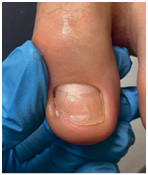

![]() ![]() ![]() Откат в динамике восстановления ногтя после протезирования Вросший ноготь

Самая распространенная и самая сложная работа, с которой мы сталкиваемся. Вросший ноготь причиняет боль, поэтому люди часто боятся обращаться за помощью – представляют себе страшную операцию с длительной реабилитацией. ![]() ![]() ![]() ![]() Работа с вросшим ногтем Одну нашу клиентку внезапная боль настигла в поездке. Она тут же решила обратиться к специалисту, но что-то пошло не так. В ближайшей студии подологии ей срезали вросший сегмент и благополучно забыли его достать. Проблема не исчезла, и девушка вновь обратилась к подологу, только уже в нашу студию. Наш специалист промыл рану, проложил тампонаду и установил титановую нить. Из-за образования грануляции рана кровила, поэтому система слетела через 3 дня. Именно для таких случаев у нас действует гарантия на коррекционные системы – в течение двух недель после установки при необходимости мы поменяем систему бесплатно. На втором приеме специалисту все-таки удалось достать вросший сегмент, который причинял столько неудобств. Сейчас девушка ходит с системой чуть послабее, и мы ждем ее на плановый прием для коррекции системы и наблюдения динамики. Хорошо, что наша героиня не стала терпеть боль и быстро обратилась за помощью повторно. Чем раньше вы направитесь к специалисту, тем больше шансов быстро и безболезненно избавиться от проблемы. Причины врастания 1. Гипергидроз стоп (повышенная потливость). 2. Неправильная обработка ногтей: когда вы обрезаете их слишком глубоко или срезаете уголки. 3. Неправильно подобранная обувь, особенно слишком узкая в переднем отделе стопы. 4. Ортопедические проблемы, например плоскостопие. 5. Травма ногтя: ноготь после травмы отрастает, дистальный валик закрывается, и стенки ногтя начинают врастать. Как идентифицировать вросший ноготь Чаще всего проблема встречается на больших пальцах ног. Тревожные сигналы: • кожа вокруг ногтя краснеет, затем на ней появляется отечность, становится больно дотрагиваться до ногтя; • из поврежденных областей начинают сочиться кровь и гной; • вросшая часть ногтя становится плотнее, болезненность переходит в хроническую форму. Топ-3 совета как избавиться от вросшего ногтя без операции Как лечить Есть два варианта – радикальный и консервативный. Радикально решают проблему хирурги – просто удаляют проблемный ноготь. К сожалению, этот метод не решает проблему полностью, очень часто она рецидивирует. Радикально решить проблему без рецидива можно, только если удалить ноготь вместе с матриксом. Но тогда ноготь уже не будет таким же красивым и ровным, как до операции. Подологи – консерваторы. Специалист аккуратно отрезает кусочек ногтя, который вызывает воспаление. Это больно? Все индивидуально: кто-то совсем не испытывает дискомфорта, кому-то приходится немного потерпеть. Но сильной боли нет – обычно страх сильнее, чем боль:) Даже дети вполне спокойно переносят процедуру. Мы работаем без анестезии, но она и не нужна, потому что в работе мы не затрагиваем ранку. Сразу после процедуры становится значительно легче, а для полного заживления требуется от недели до месяца. Вросший ноготь. Простой способ вылечить вросший ноготь без боли ![]() ![]() ![]() ![]() |